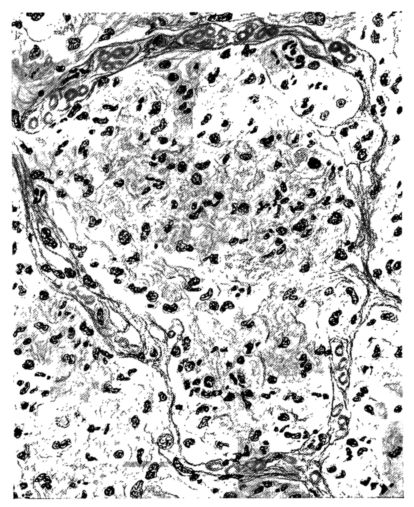

FIG. II. AUTOPSY NO. 98. DRAWING OF A SECTION THROUGH A TRACHEA SHOWING NECROTIZING HEMORRHAGIC INFLAMMATORY PROCESS OF THE MUCOSA.

The changes are less marked, perhaps, in the trachea than in its finer ramifications. The mucosa is constantly more or less destroyed and large areas, usually focal, are entirely devoid of their epithelial covering. This is replaced by a sparse exudate, composed largely of red blood cells, mucus, a small amount of fibrin, and nuclear fragments (Fig. II). It may dip into the submucosa for a short distance, but usually these indentures are associated with the ducts of the mucous glands into which the inflammatory reaction extends. A more striking feature than the exudate, however, is the edema and the congestion of the submucosa. The loose areolar tissue of the submucosa is spread widely apart, and throughout it distended blood vessels are very conspicuous. Occasionally such a vessel is broken and actual hemorrhage appears in the submucosa. Occasionally, too, the inflammation extends down the duct to the mucous gland itself, and here, also, aplastic inflammatory reaction is evident, inasmuch as the acini now stain intensely red with the cells undifferentiated from each other and specked here and there by broken remains of the dead nuclei (Fig. III). After the disease has continued for a short period, even at the end of five or six days, some regeneration of the epithelial lining may be seen (3) (Fig. IV). But despite this, the acute picture persists, and there goes on, side by side, an attempted repair characterized by epithelial regeneration and the same evidence of acute change. Since the lesion is essentially a superficial one, scars or contractures of any extent are not encountered in the trachea, even in examples of the disease that have ended fatally only after many weeks.[4]